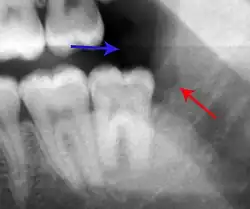

Decay (green) with apical abscess (blue)

- Radiographs utilized to find dental caries and bone loss laterally or at the apex.